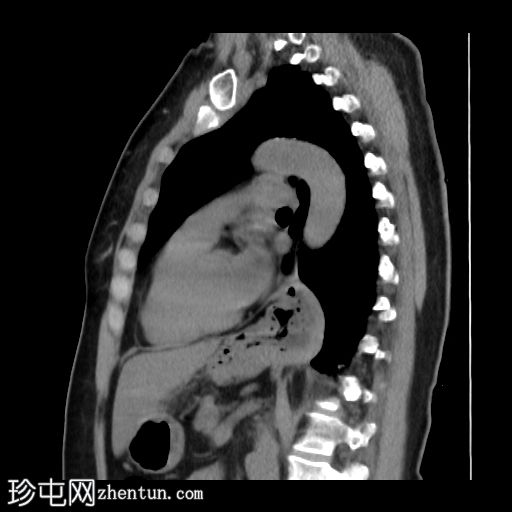

矢状位

平扫

既往行胃底折叠术部位位于膈肌上方,与透视检查结果一致。

透视和 CT 检查证实胃底折叠术已疝出到胃食管连接处上方,动态透视图像显示存在胃食管反流。